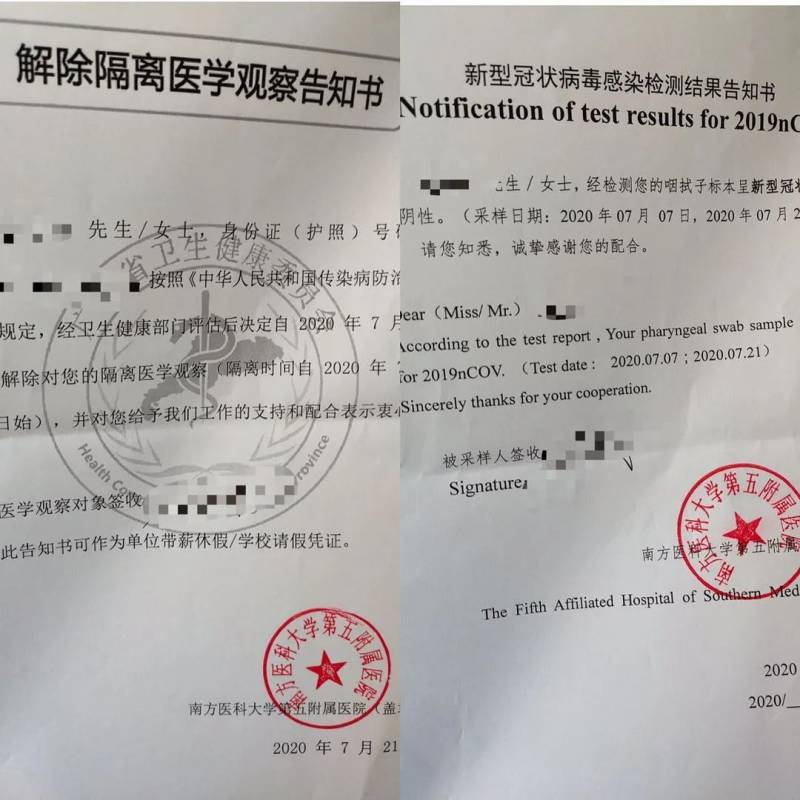

7月7日,父母从新加坡飞广州,经过14天的集中隔离医学观察。又于22日坐飞机回到家中继续14天的隔离后,14+14天,终于解除了居家隔离,自由了!

(广州14天解除隔离告知书)

(湖北14天解除隔离告知书)

进行完以上流程,拿着同意书,进入到下一个环节,就是核酸检查。

据爸爸回忆,核算测试就是微微仰著脖子,一个很细很长的棉线似的东西,塞进鼻孔里。因为塞得很深,耳朵和喉咙都感觉到了,而且还会不停的抽动,很酸的感觉,眼泪一下子就出来了。

不过不用担心,工作人员都是很专业的,并且很快就做完了。你也不用问工作人员结果,他们会告诉你回酒店等消息。